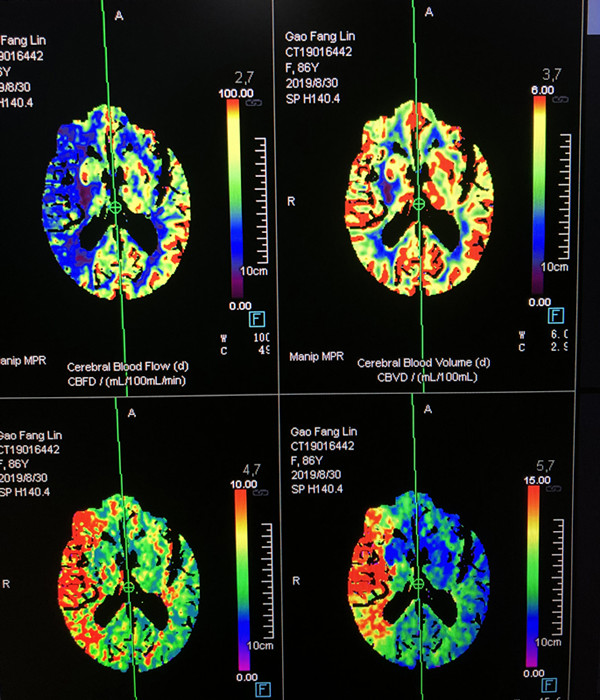

术前CTA见右侧颈内动脉闭塞

术前CTP提示右侧颈内动脉分布区血流减少